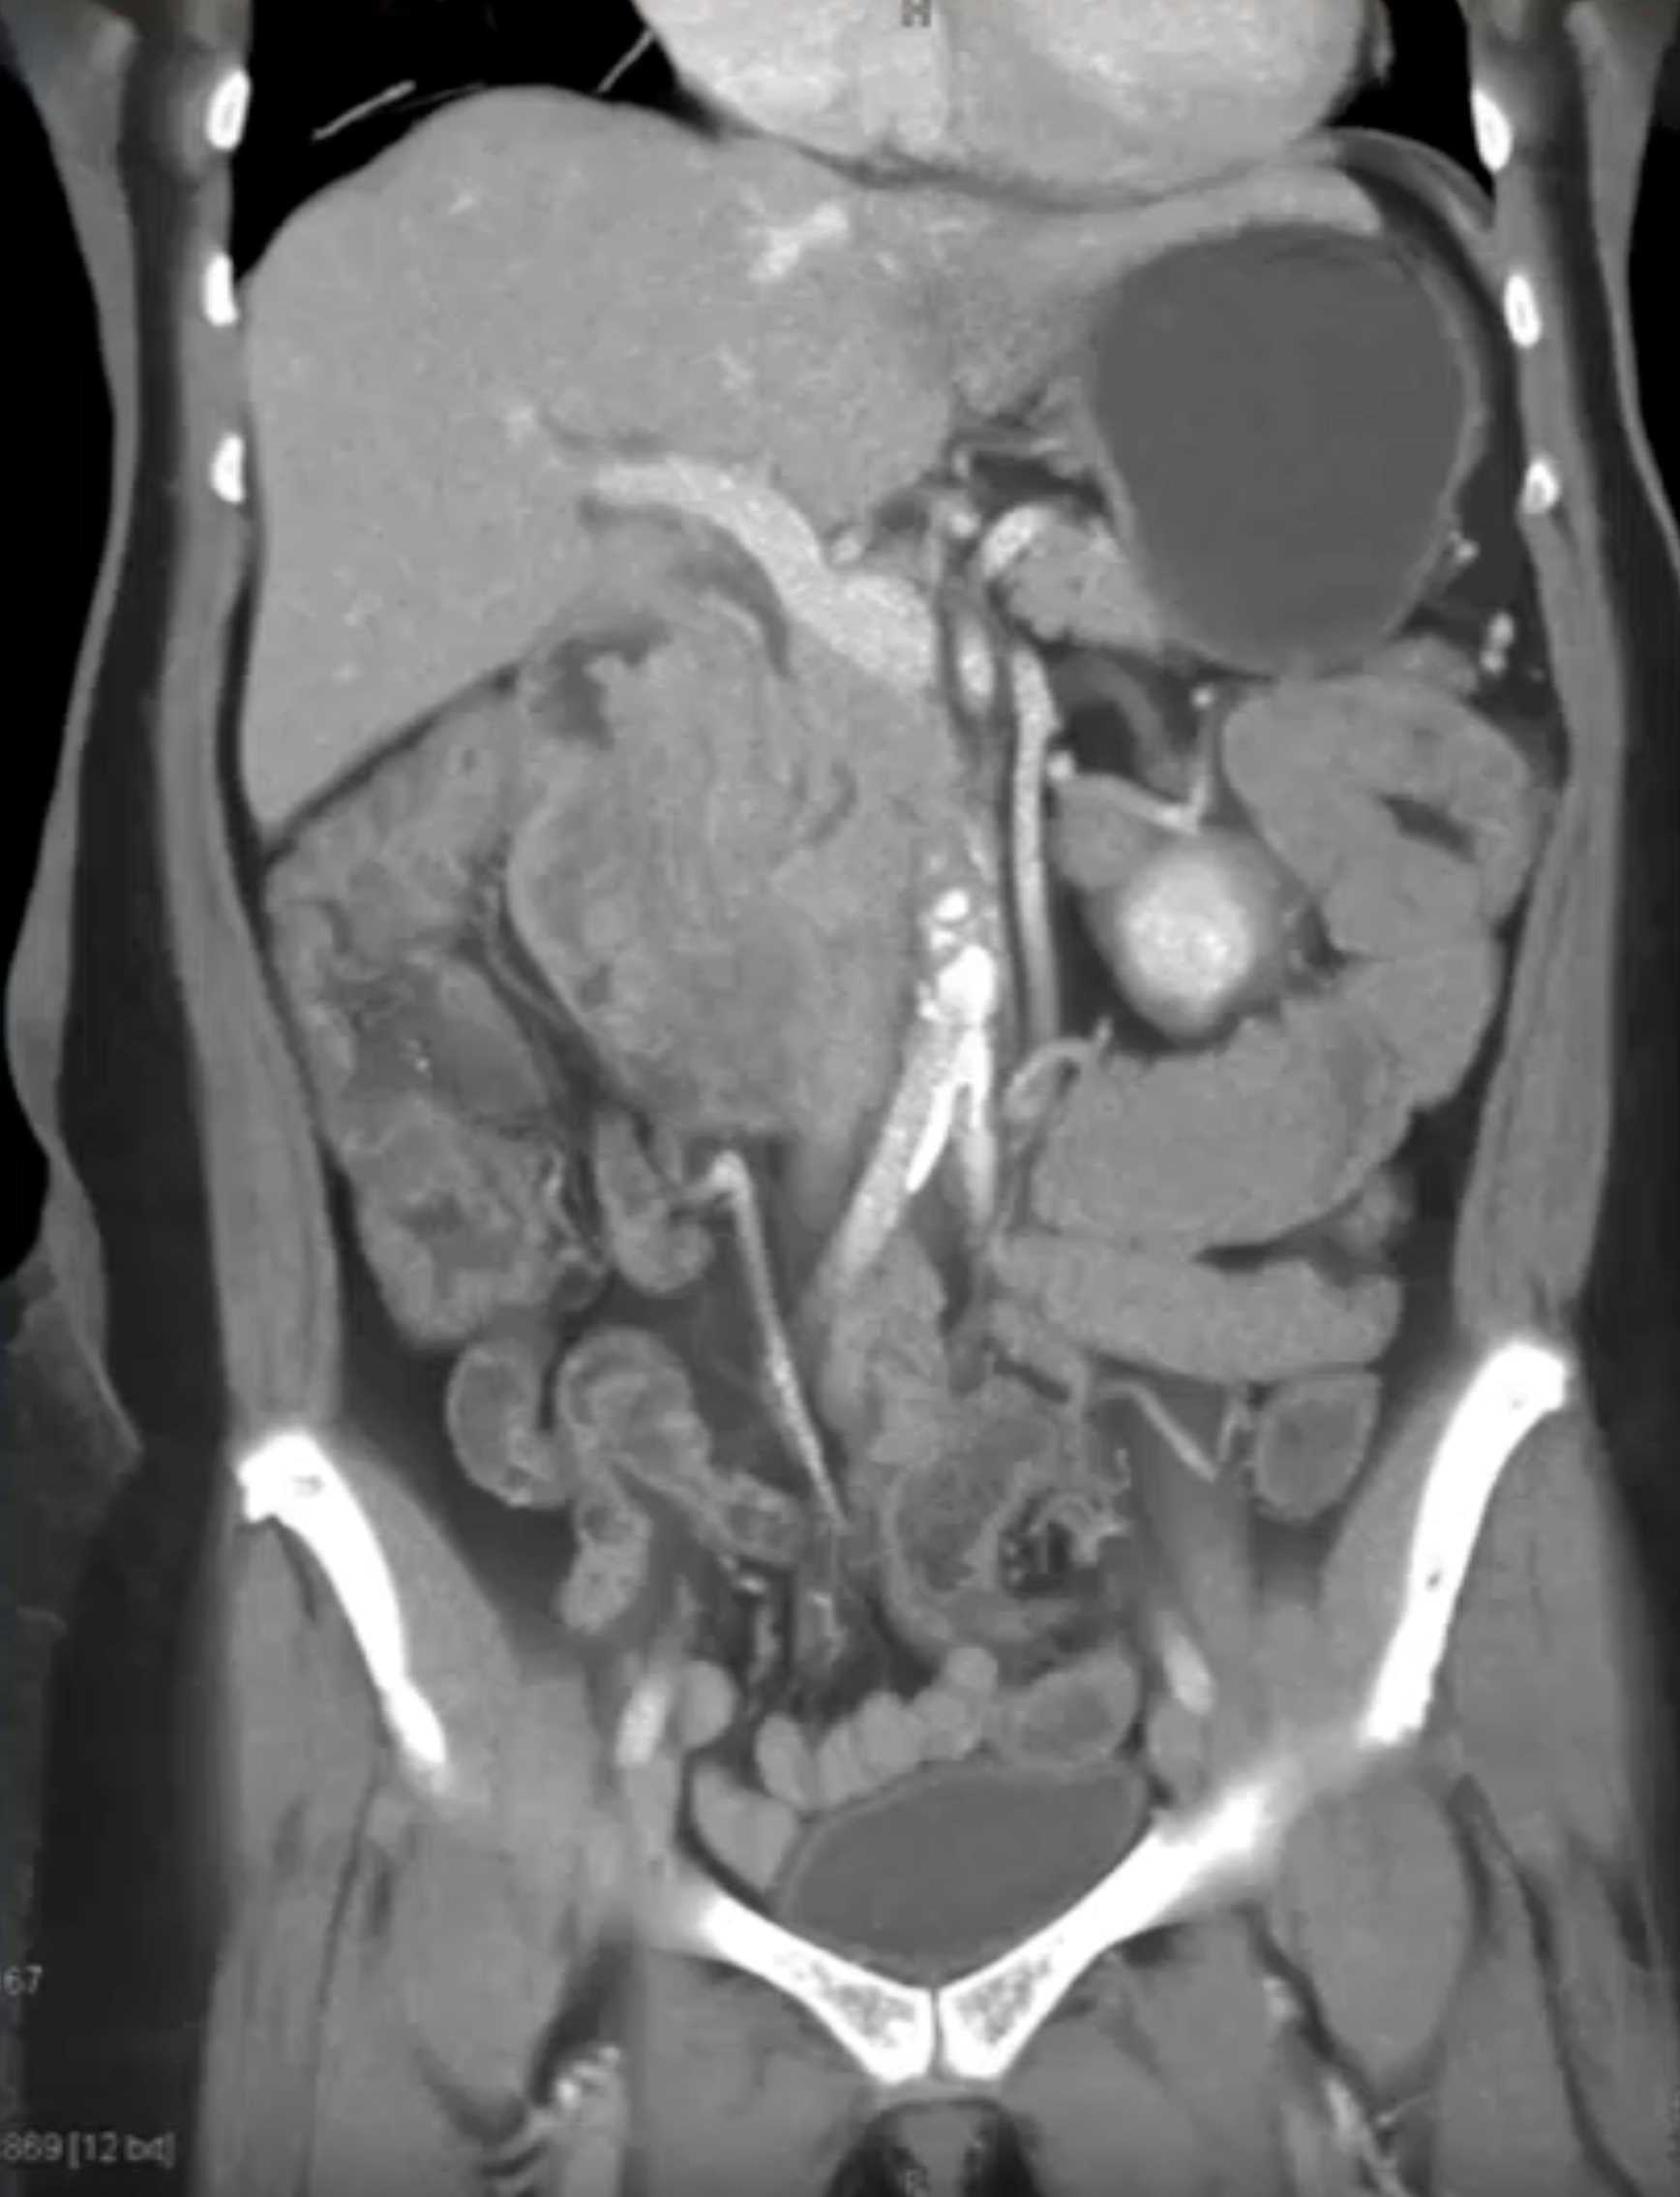

Lagre Gastric GIST Tumor